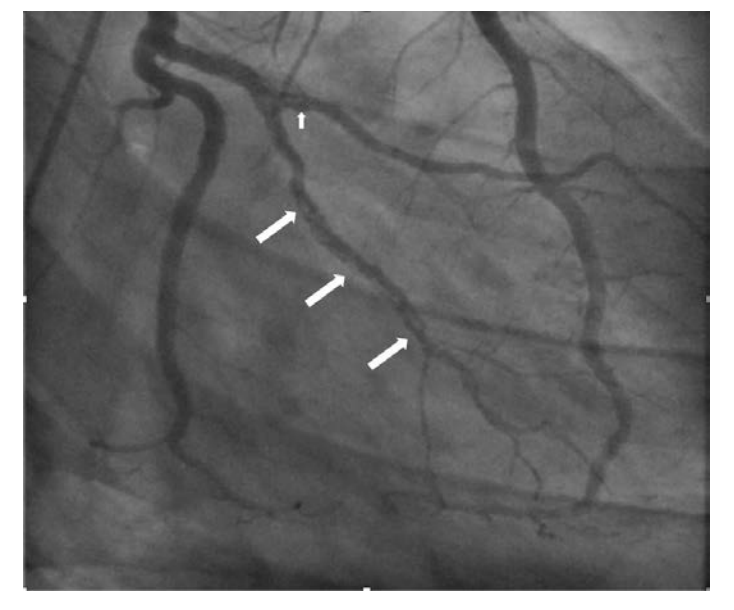

– A subsequent coronary angiogram revealed diffuse organized filling defects with TIMI III flow of obtuse marginal artery (OM) and right coronary artery (RCA) consistent with chronic thromboembolism of coronary arteries.